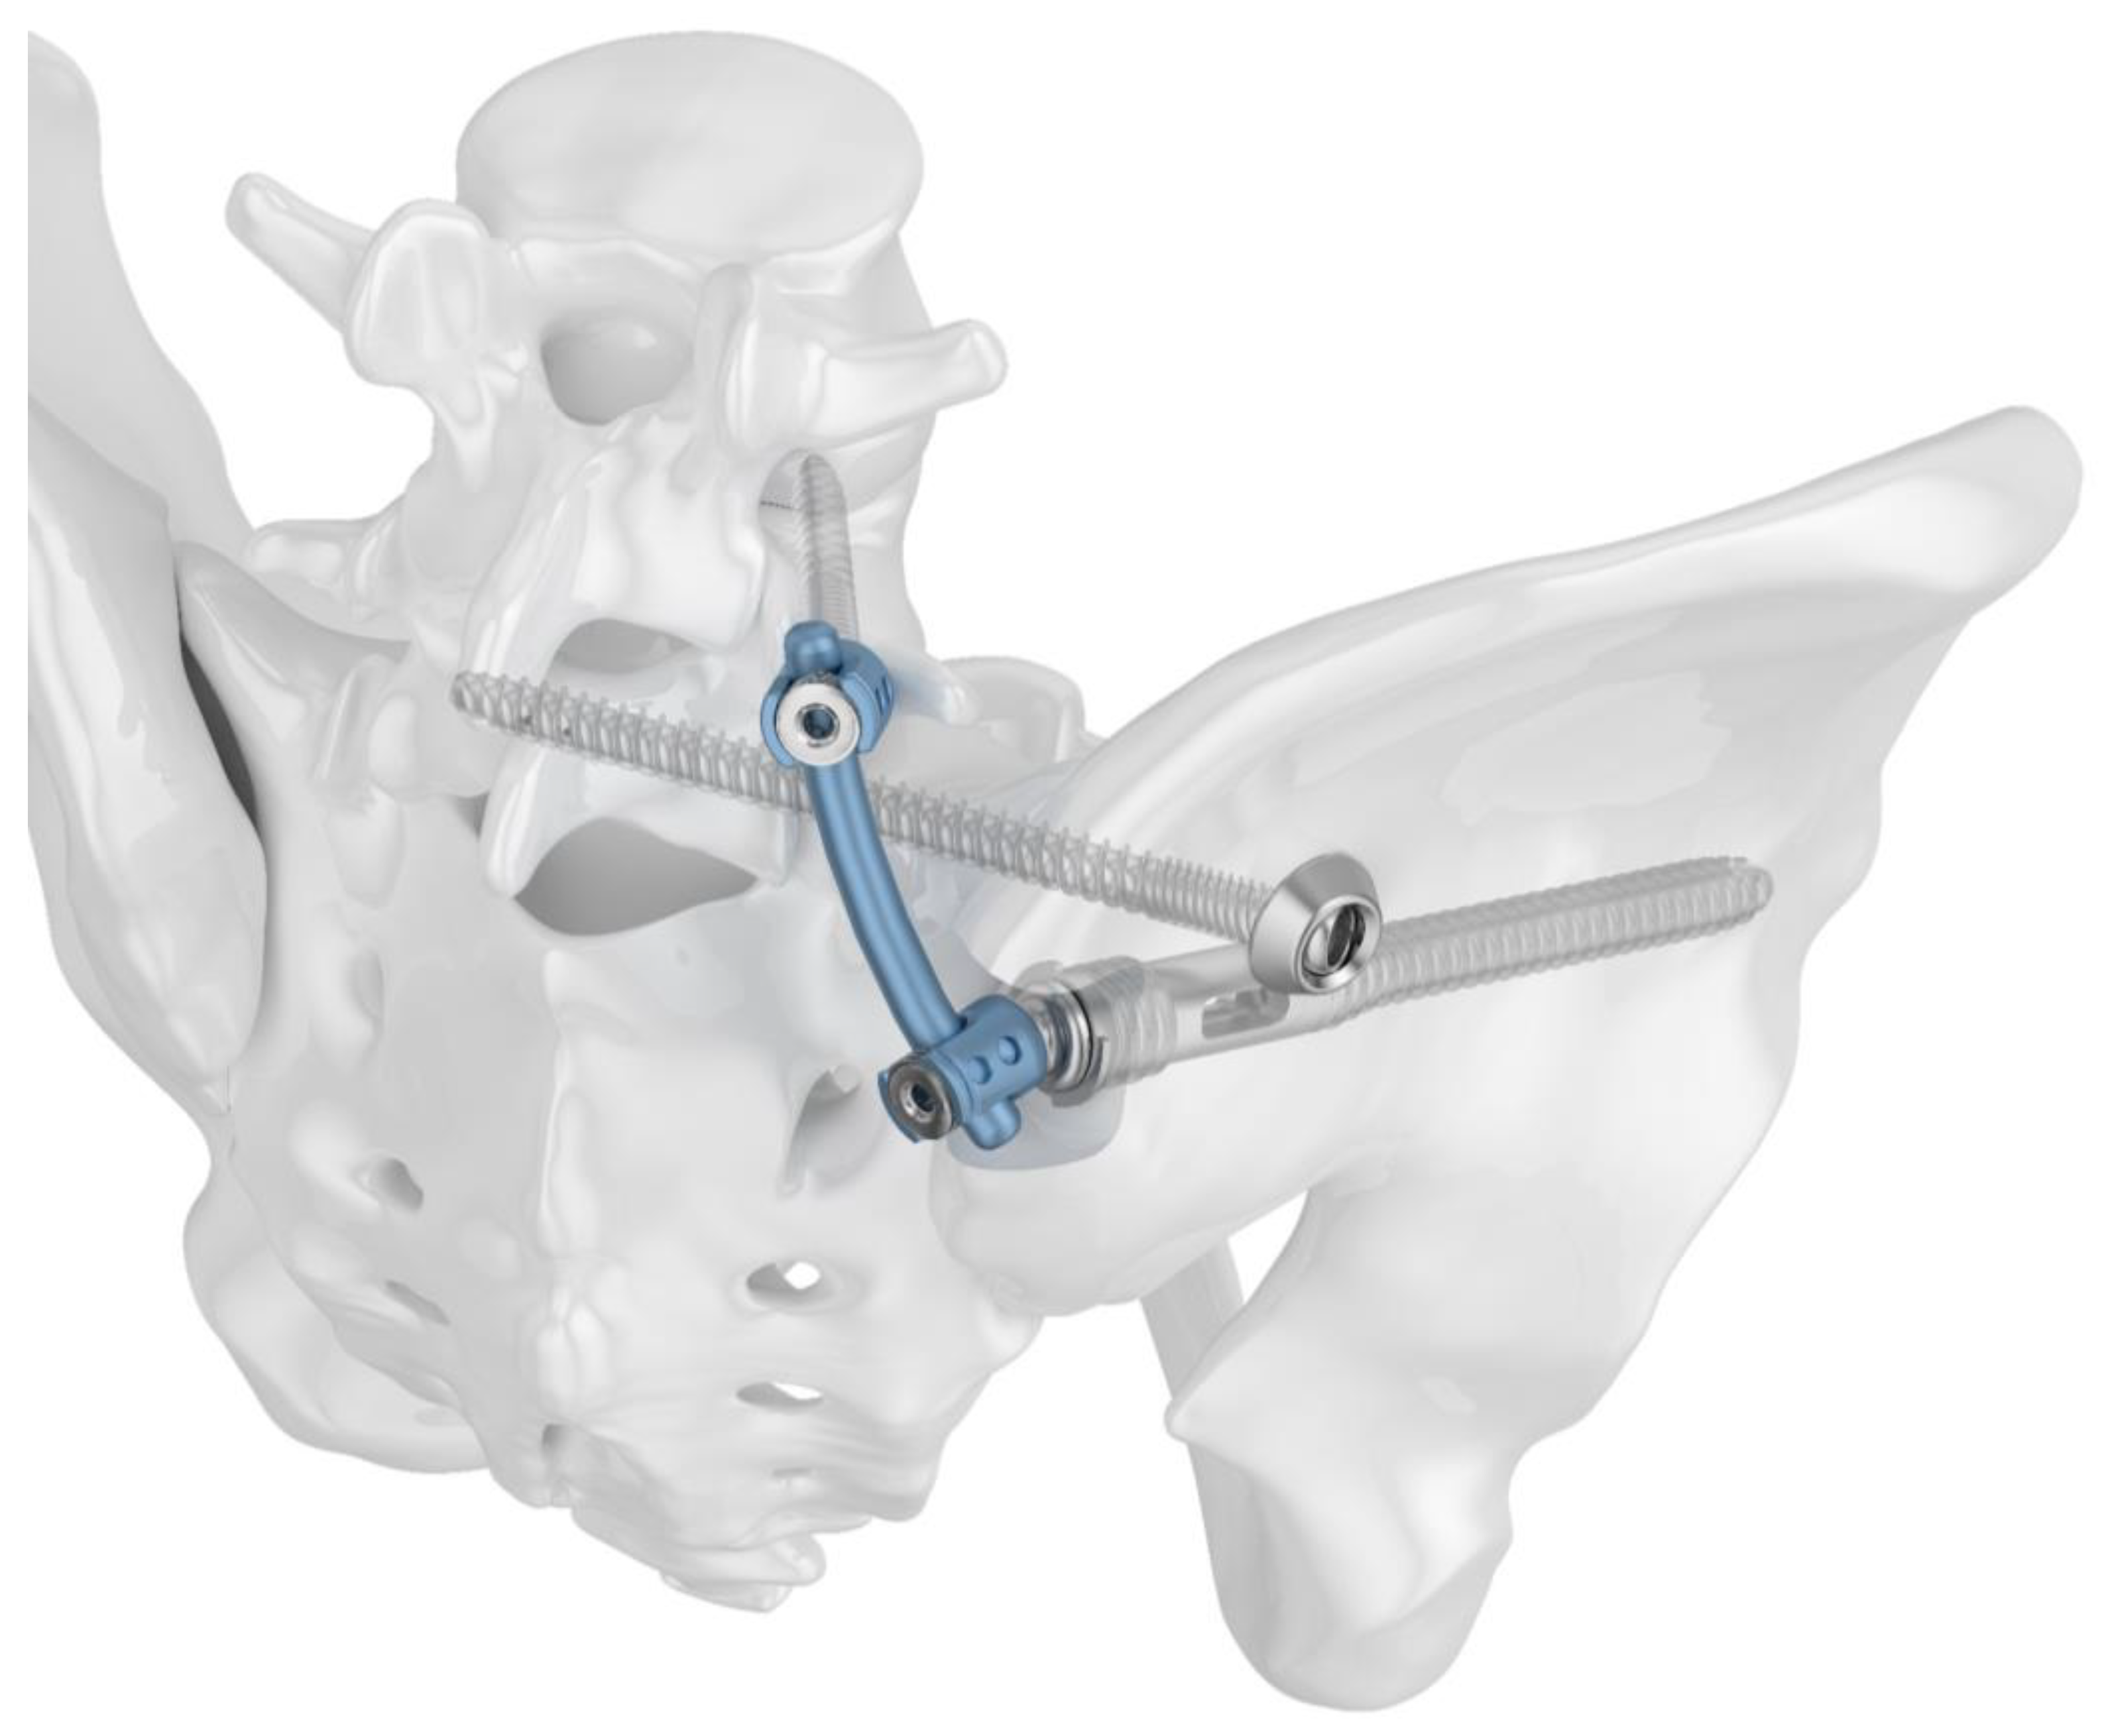

Two different implant configurations for a triangular lumbo-pelvic stabilization were tested. All of the used implants were manufactured from titanium alloy Ti6Al4V. Group I (TFS) was stabilized with the triangular fixation system TriFix (Silony Medical AG, Frauenfeld, Switzerland). This was composed of a fenestrated iliac screw with an anterior screw portion with 9.2 mm diameter and a fenestrated portion with 14 mm diameter, and an iliosacral screw with a preloaded washer. An aiming arm device was used to insert the iliosacral screw through the fenestra of the iliac screw. A polyethylene inlay in the fenestra provided quasi-angle stable fixation. The connection between the pelvic ring and the 5th lumbar vertebral body was made using the polyaxial head adapter on the iliac screw and a standard pedicle screw rod system (Figure 1). Group II (TF) was stabilized with the same implants; however, the iliosacral screw was placed separately from the iliac screw in a more cranial position (Figure 2).

Figure 1.

Image of the triangular fixation system (TFS) configuration in Group I: a fenestrated iliac screw and an iliosacral screw with a premounted washer stabilize the dorsal pelvic ring. Lumbo-pelvic stabilization is achieved by connecting the polyaxial head adapter of the iliac screw to a pedicle screw rod system.